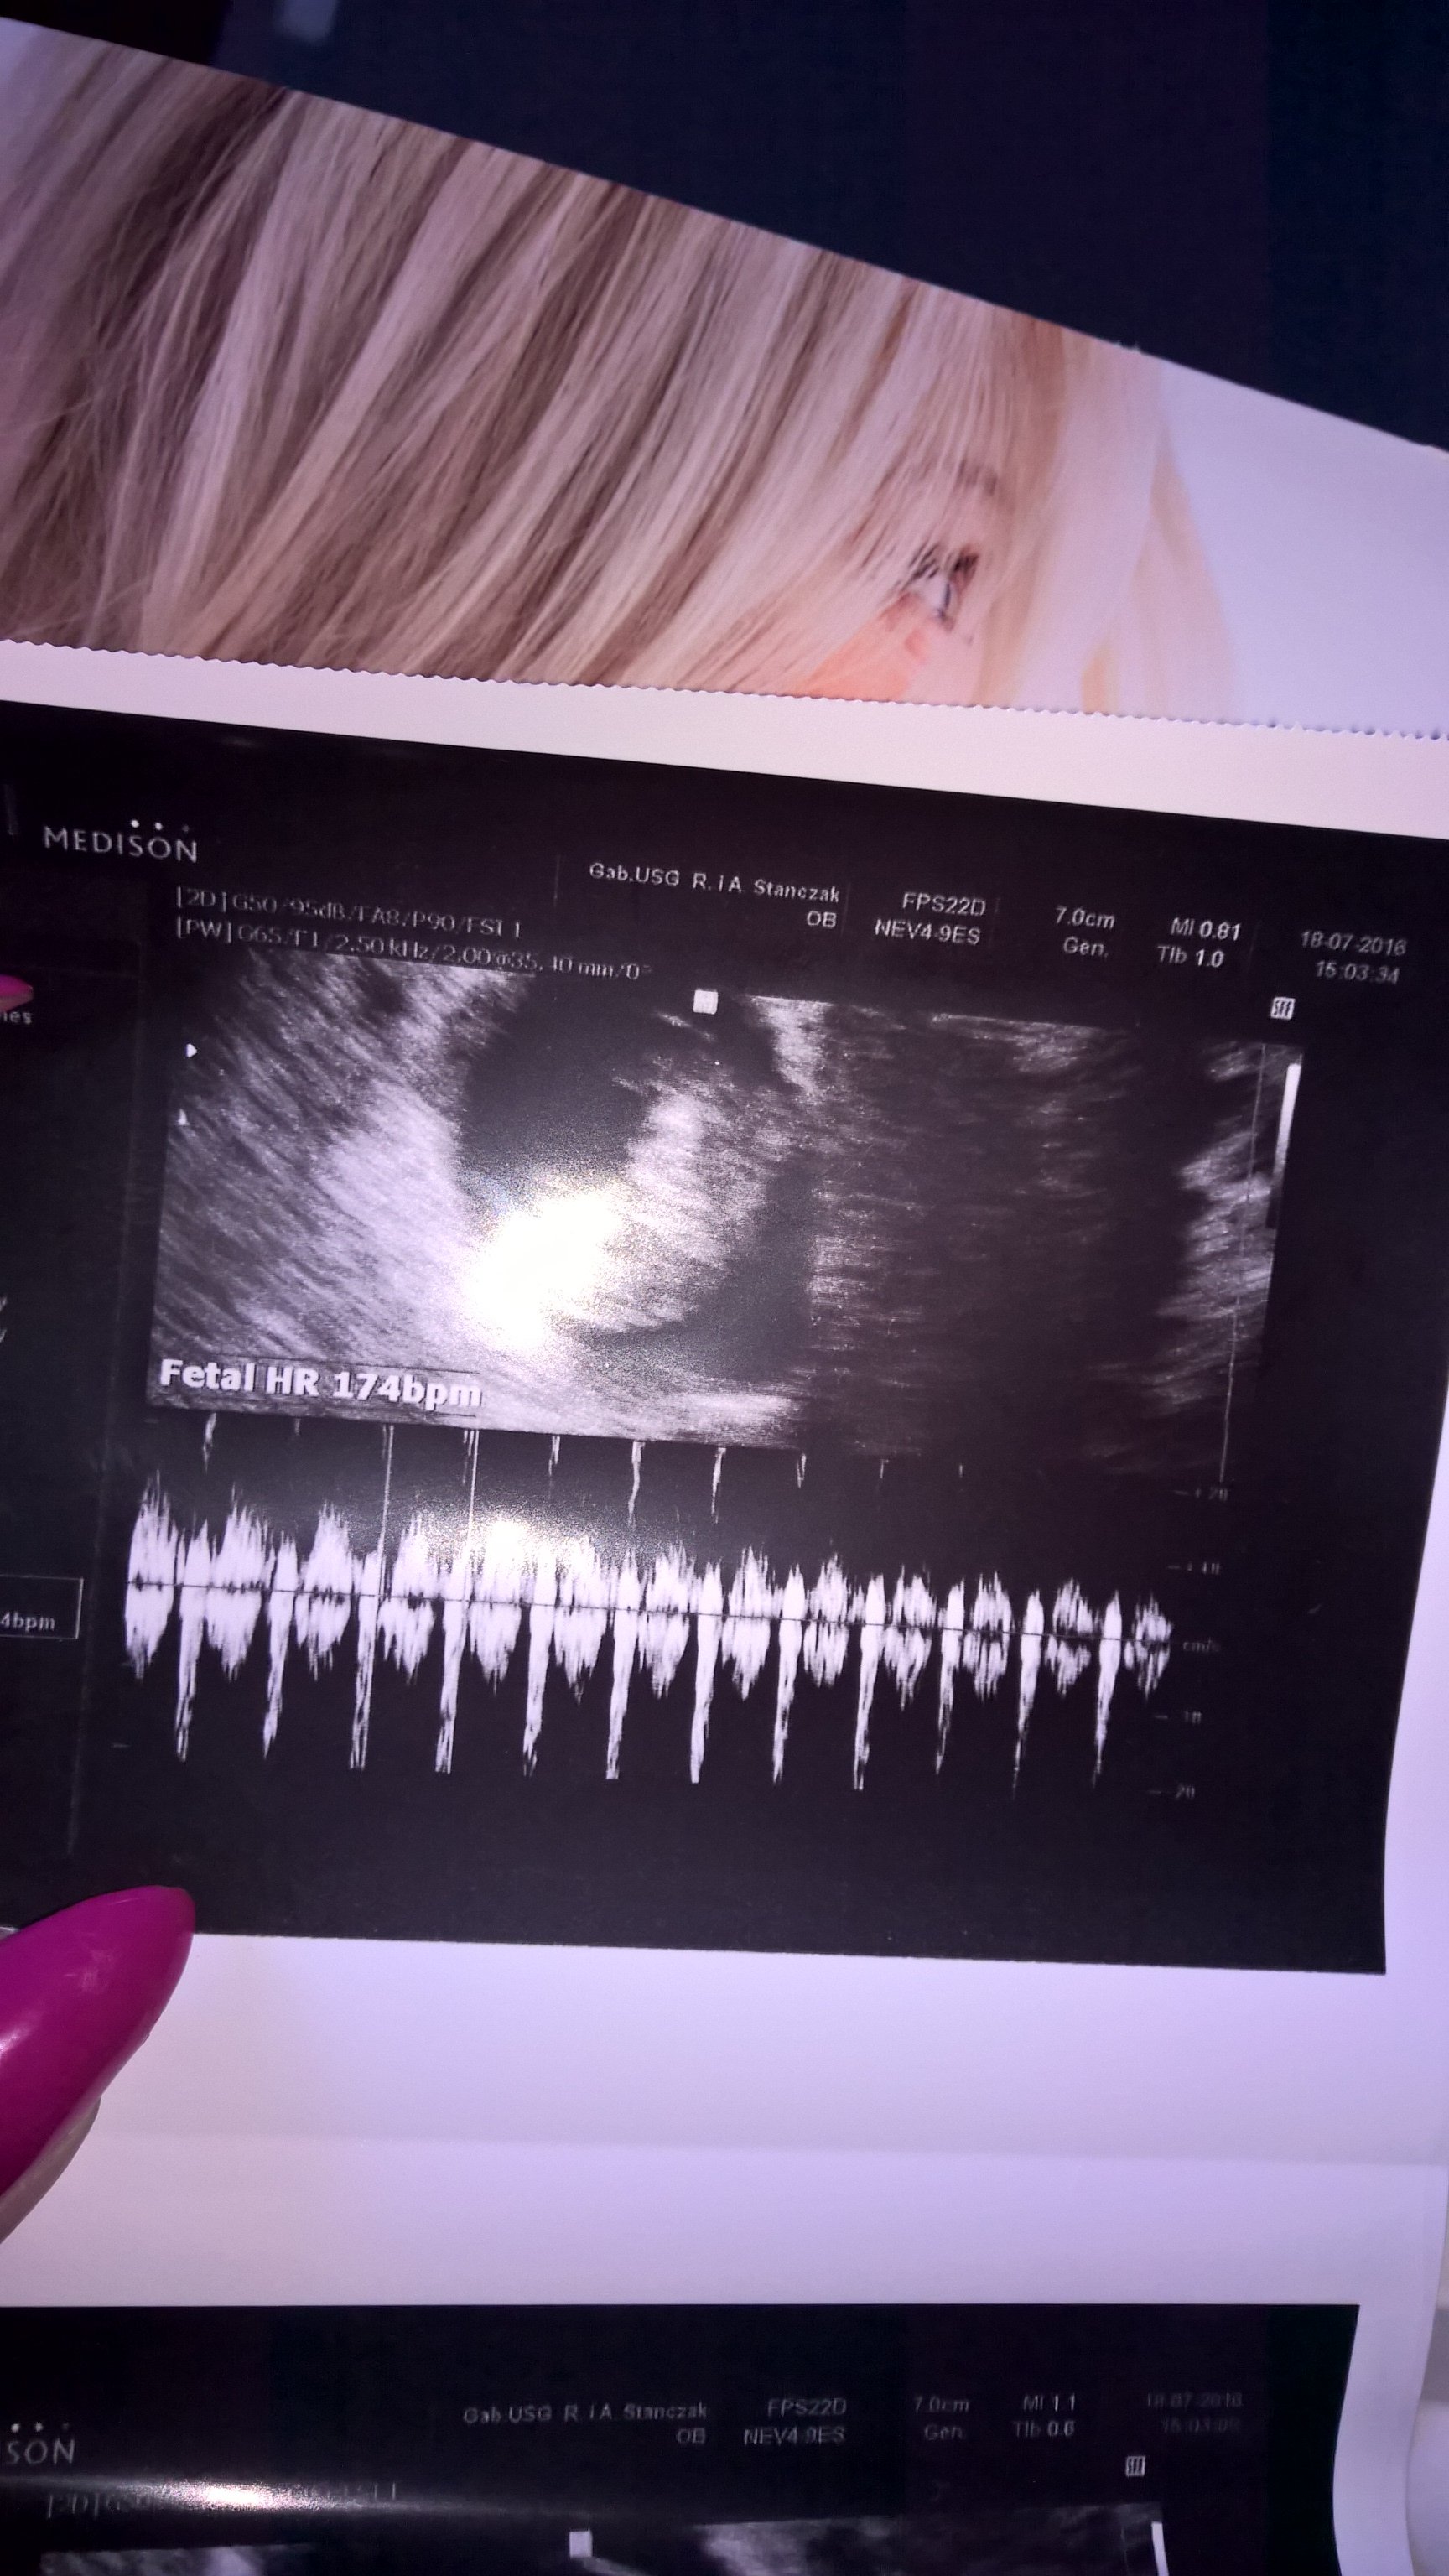

Jestem jestem :) troche sie zeszło miałam normalna wizytę No i wracałam bezpiecznie powoli :) wszystko ok, jest serduszko wg usg 7t1d wg om 6t5d, mam juz kartę ciazy i skierowanie na wszystkie badania łącznie z przeciwciałami odpornosciowymi bo ja mam minusowa grupę krwi. Takze jestem szczęśliwa. Ochrzan dostałam za to ze wzięłam Apap a miałam tylko 37.3 temp ;)